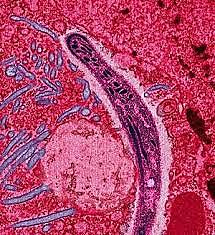

Matou mais de 1 Bilhão de pessoas e podia atacar qualquer órgão do corpo porém principalmente os pulmões é era altamente contagiosa passando pela vias aéreas e seu causador era o bacilo Koch.